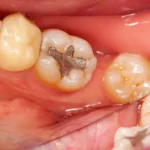

Amalgam (Silver) Fillings

Strong silver-colored fillings that last a long time and are great for back teeth.

Amalgam Fillings (Best for Strong Back Teeth)

Silver-colored but very strong. Good for chewing teeth if you don’t mind the color.